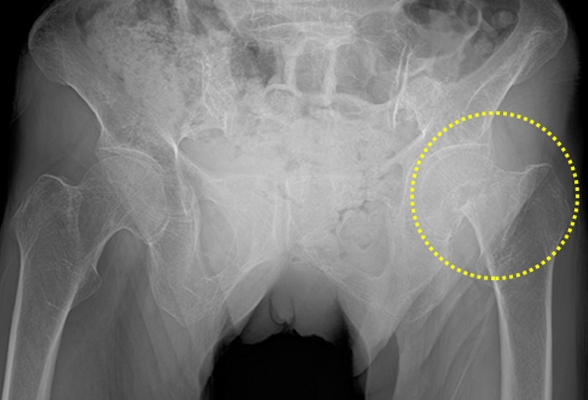

대퇴골 경부 골절

고관절은 고령으로 가면서 골절될 확률이 높아지게 되며

주로 미끄러지거나 넘어져서 발생하는 골절의 형태가

다양한데 고관절이 골절되면 극심한 통증과

걷기 어려워져 수술이 필요합니다.

치료법

수술치료 : 인공관절 치환술